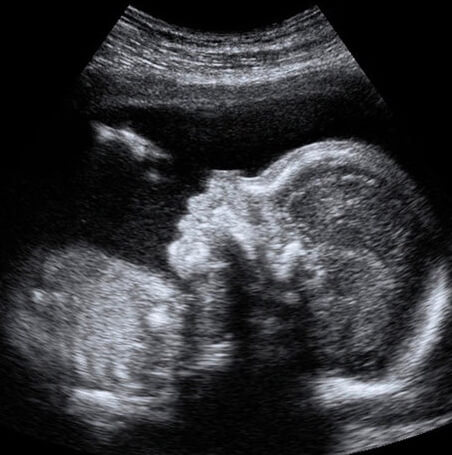

37 Haftalık Bebeğin Ultrason Görüntüsü

Bu fotoğraflarla bebeğinizin ultrason görüntülerini karşılaştırdığınızda, birçok farklılık olduğunun farkındayız; çünkü özellikle hamileliğin son haftalarında, bebeklerin görüntülerinde ciddi farklılık olması doğaldır. Ancak bu görüntüleri bebeğiniz hakkında bir referans olarak alabilirsiniz.

• 37 haftalık bebek ultrasonunda, bebeğin yüz hatları, ağzının burnunun şekli vb. çok daha net şekilde gözükmektedir.

• Bebeğiniz tıpkı yenidoğan bir bebek gibi uyuyup uyanmakta, parmağını emmekte ve hatta gülmektedir.

• Bu hafta muhtemelen bebeğinizi baş aşağı dönmüş bulacaksınız ve bebeğinizin doğuma hazırlandığına şahit olacaksınız.

• Eğer bebeğiniz hâlâ baş aşağı dönmediyse, bir hafta daha vakti vardır; ancak doktorunuz bebeğinizin duruşunun değiştirilmesi için size tekrar bir randevu verebilir. Böyle bir durumda endişelenmenize gerek yoktur; çünkü baş aşağı dönmeyen inatçı minikler de doğuma kadar doğru pozisyonu alabilmekte ve kolay bir doğum yaşayabilmektedir.